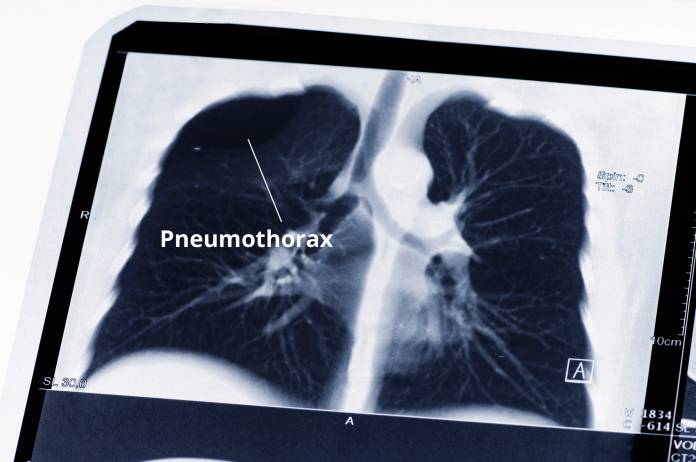

Unter Umständen kann es beim Schlüsselbeinbruch sogar zu einer Verletzung der Lunge mit möglichen Atemproblemen (etwa beim Pneumothorax = Zusammenfallen eines Lungenflügels) kommen.